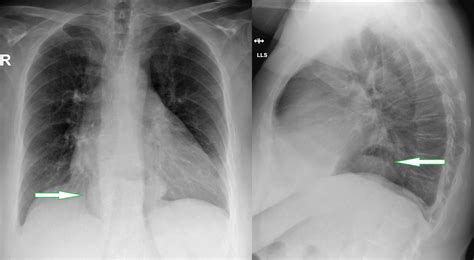

Chest X-ray: Provides a basic view of the chest and can show the presence of a hernia.